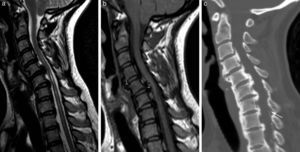

Resonancia magnética de columna cervical. Imágenes potenciadas en FSE T2 en plano sagital (a), en plano coronal (b) y plano axial (c, online). 1) Proceso odontoides. 2) Ligamento transverso y cruzado. 3) Clivus. 4) Arco anterior de atlas. 5) Arco posterior de atlas. 6) Amígdala cerebelosa. 7) Cuerpo de axis. 8) Ligamento longitudinal posterior (LLP). 9) Membrana tectorial 10) Masas laterales de atlas. 11) Ligamento apical de la apófisis odontoides 12. Ligamento longitudinal anterior (LLA). d) Imagen potenciada en FSE T2 de la columna cervical completa (online); se visualiza la continuidad de los ligamentos LLA (1). LLP (2).

Resonancia magnéticaLa obtención de la imagen en RM se basa en la combinación de planos sagitales y axiales en diferentes secuencias de pulso (tabla 1, online). Las secuencias potenciadas en T1 tienen una gran resolución de contraste y nos proporcionan la imagen anatómica. Por su parte, las secuencias potenciadas en T2 y eco de gradiente T2 tienen un efecto mielográfico y permiten delimitar los discos y la médula que queda limitada por el líquido cefalorraquídeo (LCR) (fig. 2)5,6.

Para el estudio axial, las diferentes secuencias de pulso tienen unas ventajas y unos inconvenientes. Con las secuencias eco de gradiente se diferencia mejor entre el componente óseo osteofitario y el disco, y permite diferenciar entre la sustancia gris y la sustancia blanca; las secuencias 3D FSE con pulso Drive (mantienen el efecto mielográfico T2 con un TR corto) valoran las emergencias radiculares con mayor resolución sin el artefacto de flujo de LCR. Las técnicas sensibles al agua, T2 con supresión química de la grasa o STIR permitirán visualizar mejor el incremento del agua extracelular, el edema, y son importantes para diferenciar el edema intraóseo debido al contenido graso de la médula ósea y de las partes blandas (fig. 2)5,7–9.